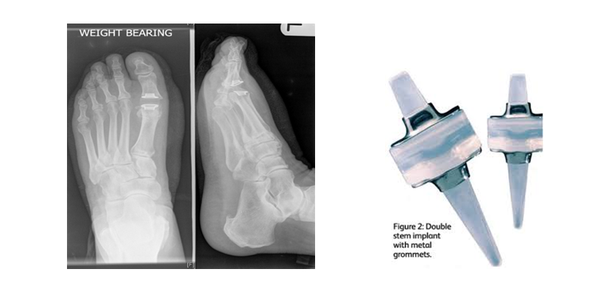

This is made by clinical examination and X-rays. The severity of the joint disease on X-ray can vary from mild to severe, although this does not necessarily correlate directly with the symptoms experienced.

Joint implant

This operation is recommended for those with moderate to severe degenerative joint disease. The silicone joint implant has a likely life span of 10-15 years. They have been used widely in the UK and US over the past 20 years. The procedure involves making an incision along the top of the big toe joint, removing both sides of the joint and placing a silicone hinged joint in the remaining space. They are not indicated in patients who have an active lifestyle or the under the age of 65 years.